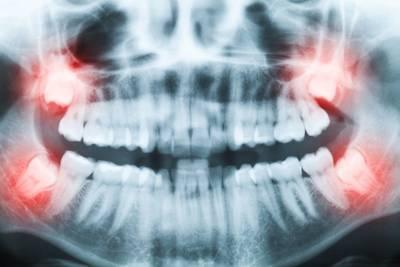

X-rays showing the need for a tooth extraction Elk Grove Wisdom teeth are a third set of molars we typically get in our late teens or early twenties. While they can help you chew, they are so far back in the mouth that they create issues for many people.

One common problem with wisdom teeth is insufficient space in the jaw to accommodate them. This can lead to crowding and a range of problems, including:

Our dentists will perform an exam and take x-rays to evaluate the position of the teeth and their roots. If wisdom teeth are causing problems or are likely to cause problems in the future, they will likely recommend removing them.